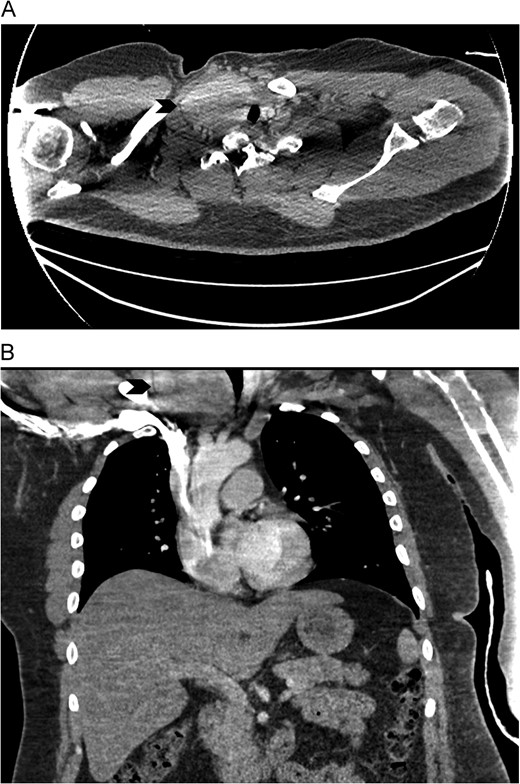

CT Chest with contrast showed an enlarged right lobe thyroid gland with retrosternal extension causing compression and deviation of trachea (arrow). (A) axial view. (B) coronal view. CT scan.